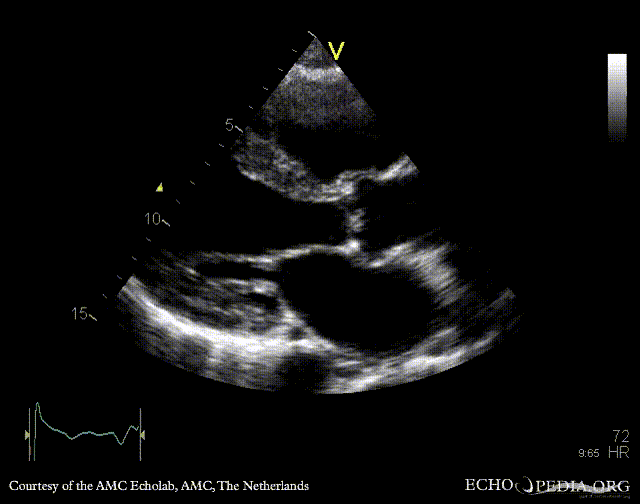

E00431.gif E00432.gif

PLAX: thickend aortic valve and mitral valve PSAX: flattening of IAS, enlarged right ventricle